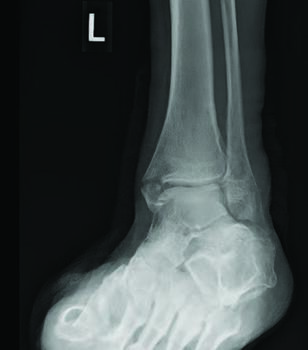

There are several studied and suggested surgical fixation options for treating complicated diabetic ankle fractures. As mentioned earlier, inappropriate treatment of these injuries can often lead to complications including the worst case scenario of Charcot arthropathy, and potential resultant limb loss. Hence, the common fundamental goals currently used for Charcot reconstruction also apply in ankle fracture fixation for patients with complicated diabetes.7 Specifically, these include obtaining a fixation construct with maximum rigidity and absolute stability, extending the fixation beyond the immediate zone of injury and planning incisions to minimize soft tissue trauma and optimize healing.4 Some fixation constructs suggested in recent literature include: circular external frame fixation; internal fixation using screws and plates; tibiotalocalcaneal (TTC) nail construct; and even locked fibular intramedullary nail fixation.4,8-10

Facaros and colleagues presented a case report of a patient with diabetes and neuropathy who sustained a displaced fibular fracture with significant joint subluxation and syndesmotic injury.11 Subsequent surgical intervention consisted of ORIF with plate fixation, multiple pro-syndesmotic screws and application of a multiplanar circular external fixator. This allowed a maximally stable and rigid construct and also allowed the patient to fully weight bear postoperatively on the external fixator. The patient underwent removal of the external fixator after 12 weeks without any long-term sequelae.11The use of multiple syndesmotic screws regardless of a syndesmotic injury is repeatedly suggested in the literature, as it allows for a more mechanically stable construct.4